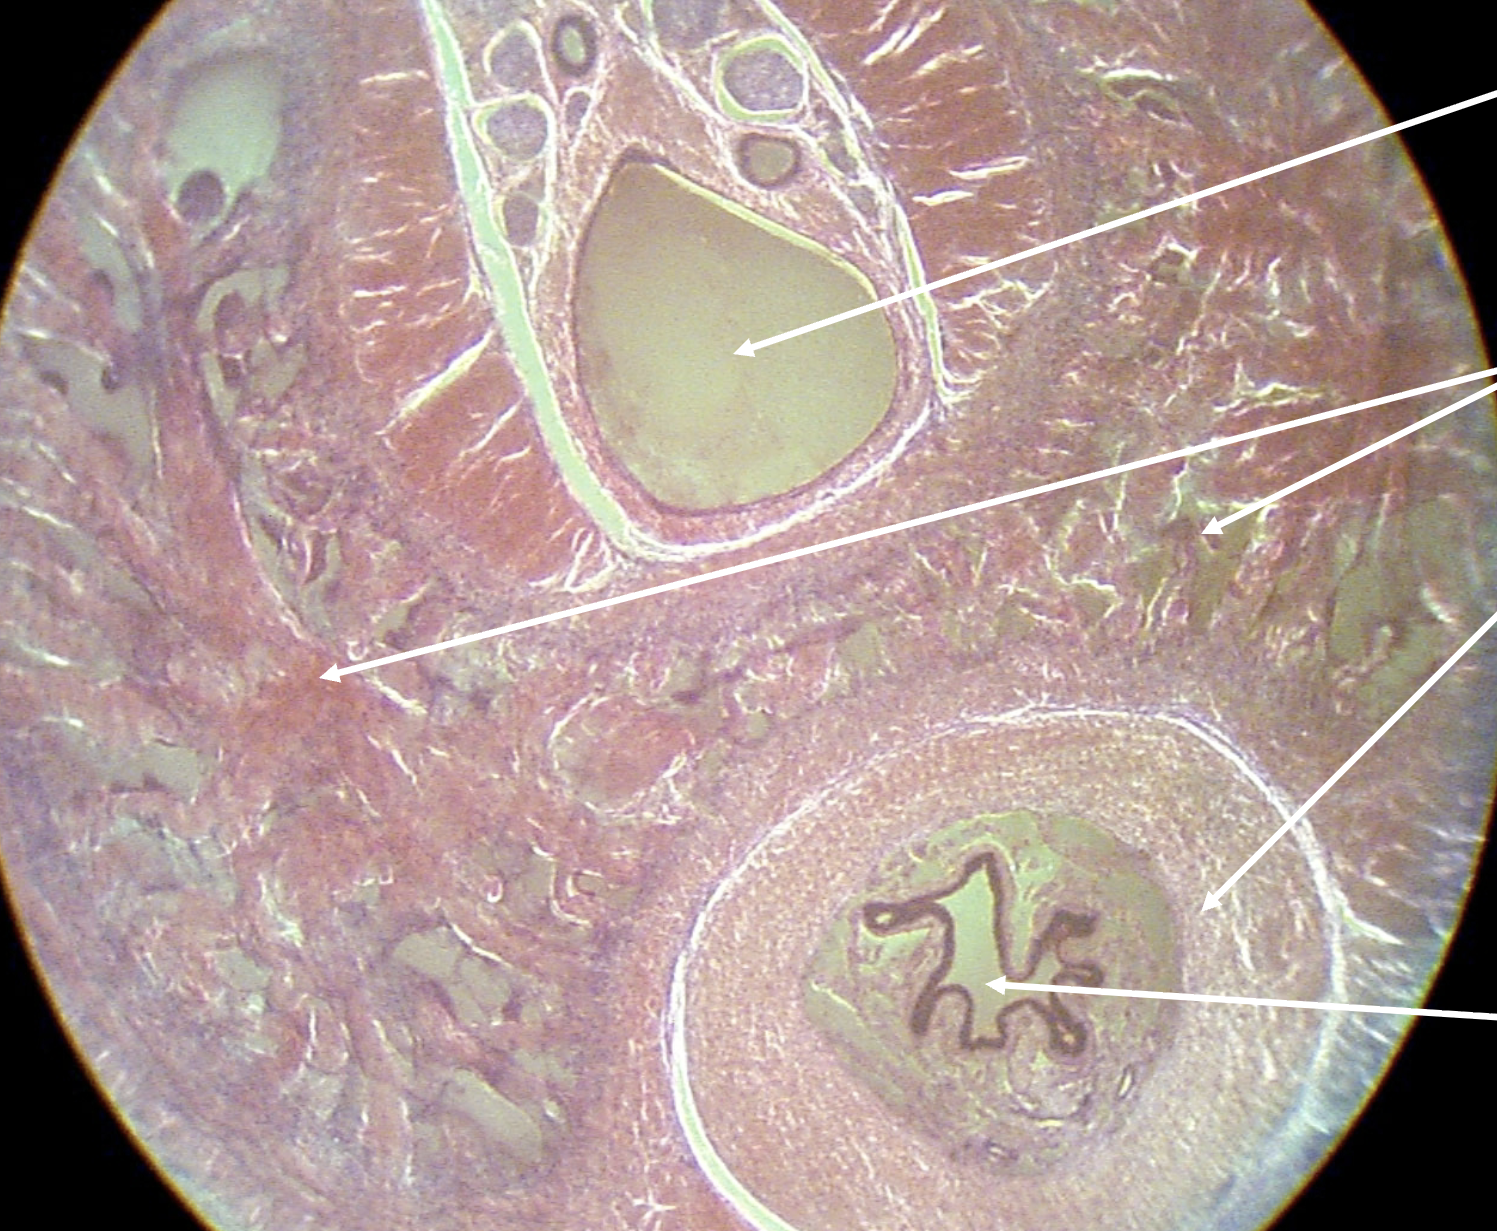

Seminiferous tubules

What structure is being depicted in this cross section?

Testis

What structures are being indicated by #1?

Sertoli cells

What structure is being indicated by the white circle?

Lumen

Leydig cells

What structures are being indicated by the leftmost arrow?

What structures are being indicated by the rightmost arrow?

Spermatogonia

What structures are being indicated by the above arrow?

Seminiferous epithelium

What structures are being indicated by the lower arrow?

Spermatids